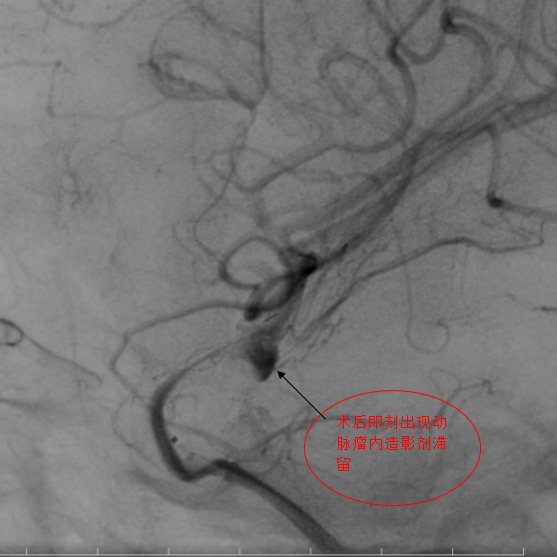

第一例手术的患者确诊为眼动脉动脉瘤合并后交通段动脉瘤,属于多发复杂动脉瘤,治疗难度倍增。团队通过置入血流导向后,动脉瘤内即可形成造影剂滞留,手术过程30分钟,患者术后2天出院。